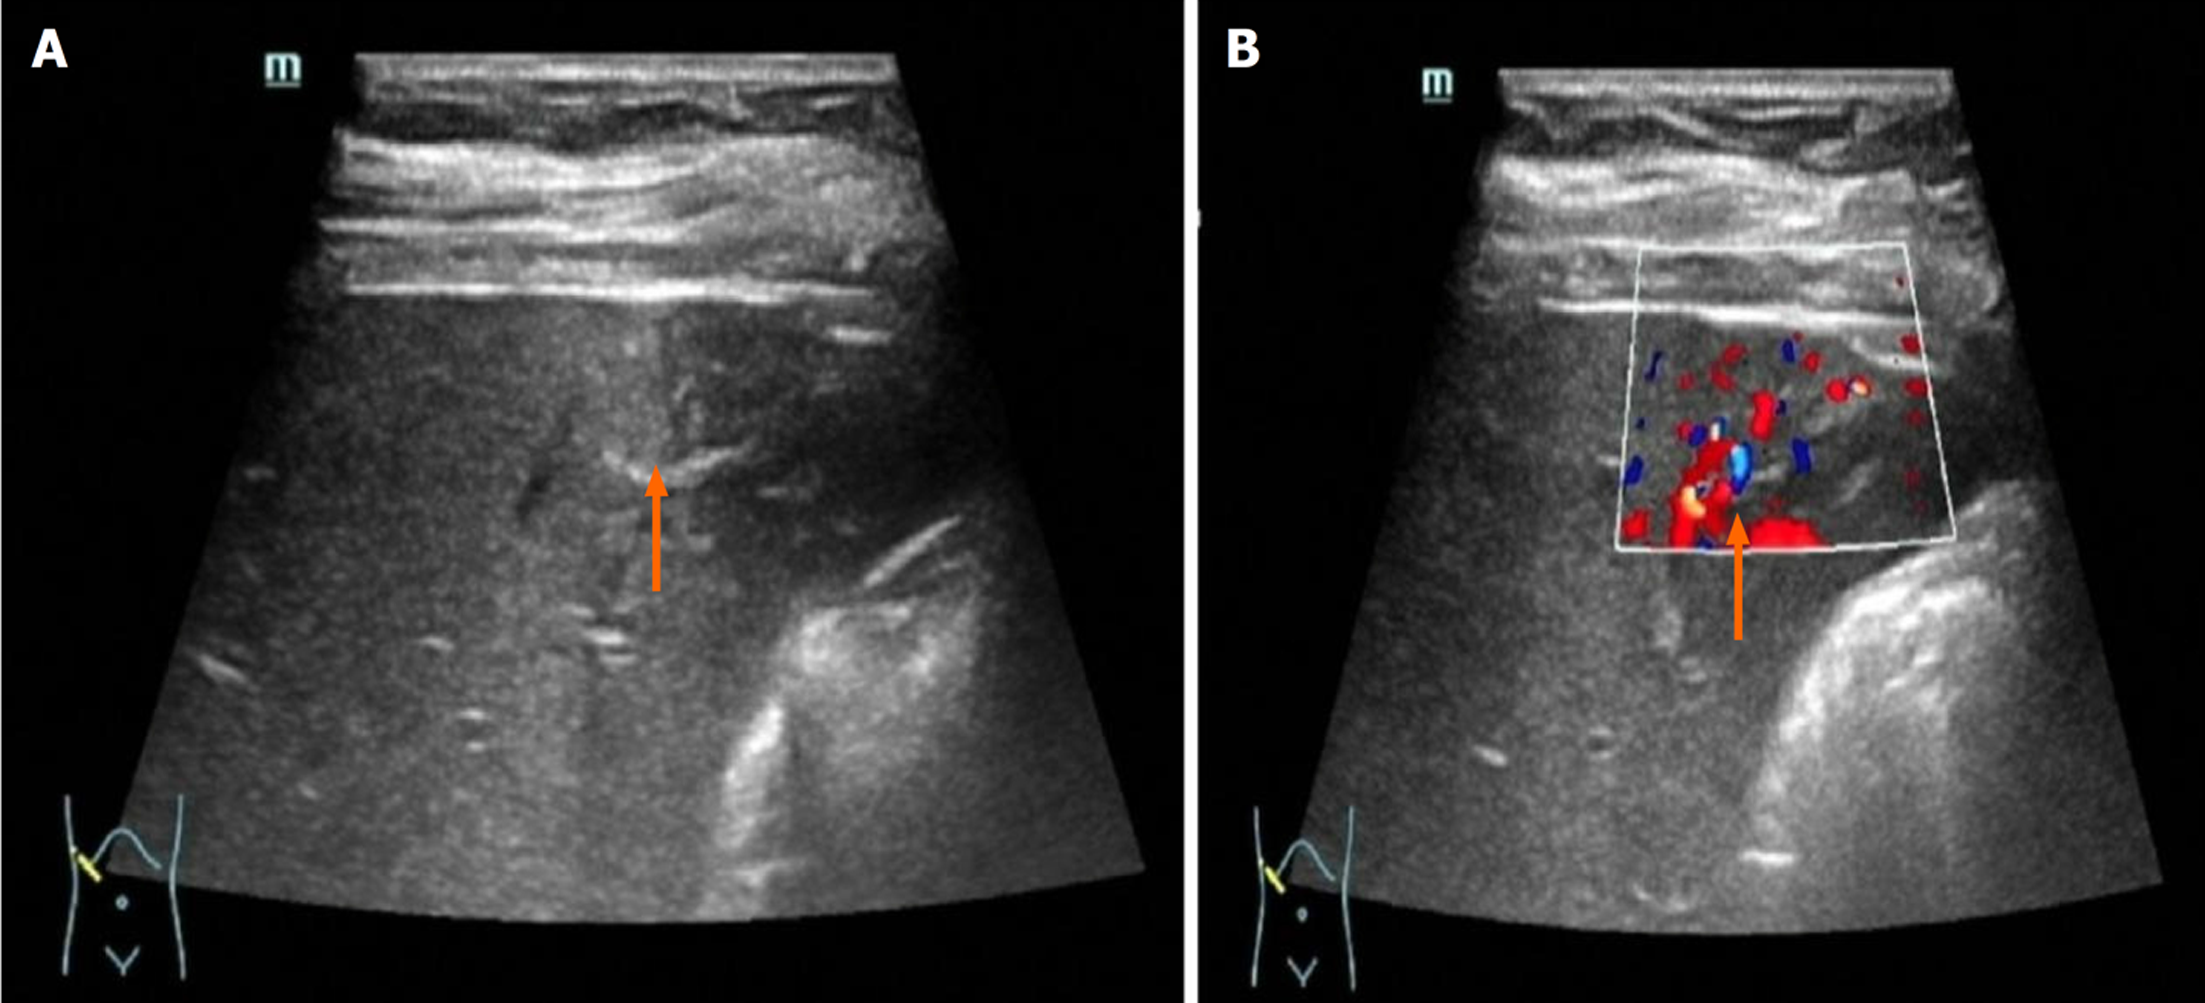

正常肝与脂肪肝均早于肝实质增强, 相对肝实质增强-消退变化大多表现为快进慢出, 无慢进慢出; 肝硬化均迟于肝实质增强, 中央瘢痕检出率显著升高, 相对肝实质增强-消退变化均表现为慢进慢出. 整体比较显示, 不同肝背景患者相对肝实质增强时间、中央瘢痕检出情况、相对肝实质增强-消退变化情况比较, 差异有统计学意义(P<0.05); 进一步的卡方分割法比较显示, 肝硬化患者迟于肝实质、中央瘢痕、慢进慢出显著高于正常肝、脂肪肝患者(P<0.0167); 不同肝背景患者其他CEUS表现比较差异均无统计学意义(P>0.05). 见表3和表4. 不同肝背景患者CEUS表现见图2.

本研究结果显示肝硬化背景对FNH CEUS表现产生显著影响, 而脂肪肝与正常肝之间差异无统计学意义, 肝硬化组100.00%表现为迟于肝实质的增强和慢进慢出模式. 分析其原因发现, 首先肝硬化患者存在肝窦毛细血管化, 可使造影剂通过时间延长[21]; 其次肝硬化门脉压力梯度可较正常肝升高, 导致门脉灌注减少; 最后肝硬化患者肝动脉缓冲效应失调, 使动脉期增强峰值时间延迟, 以上肝硬化特有的血流动力学特点使得FNH患者CEUS表现出不同于正常肝、脂肪肝的征象[22]. 由于脂肪肝患者未进展至肝硬化, 肝血管结构变异与肝组织纤维化程度较轻, 尚可代偿, 使其CEUS表现与正常肝相同. 本研究中肝硬化组中央瘢痕检出率达73.33%, 显著高于其他组, 这与肝硬化背景下纤维间隔增宽有关. 本研究发现正常肝、脂肪肝患者相对肝实质增强时间、中央瘢痕检出情况、相对肝实质增强-消退变化情况等方面比较, 差异无统计学意义, 这与近期研究[23]结果一致, 表明脂肪肝不影响FNH的CEUS表现, CEUS对脂肪肝患者的FNH诊断仍保持较高可靠性.